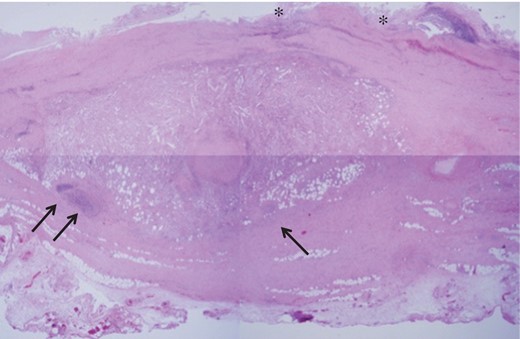

He recovered uneventfully, and postoperative contrast-enhanced CT revealed a patent graft and a decrease in the retroperitoneal mass (Fig. 1D). Histopathologic examination demonstrated excessively thickened tunica adventitia with infiltration of inflammatory cells such as lymphocytes and fibrosis (Fig. 3). The patient was discharged without subjective symptoms on postoperative Day 10.

Light microgram of the hematoxylin and eosin-stained aortic wall revealing the collapsed structure of the tunica intima (single asterisk), and the marked thickening in the tunica adventitia due to infiltration by inflammatory cells (black arrows) accompanied with fibrous proliferation.